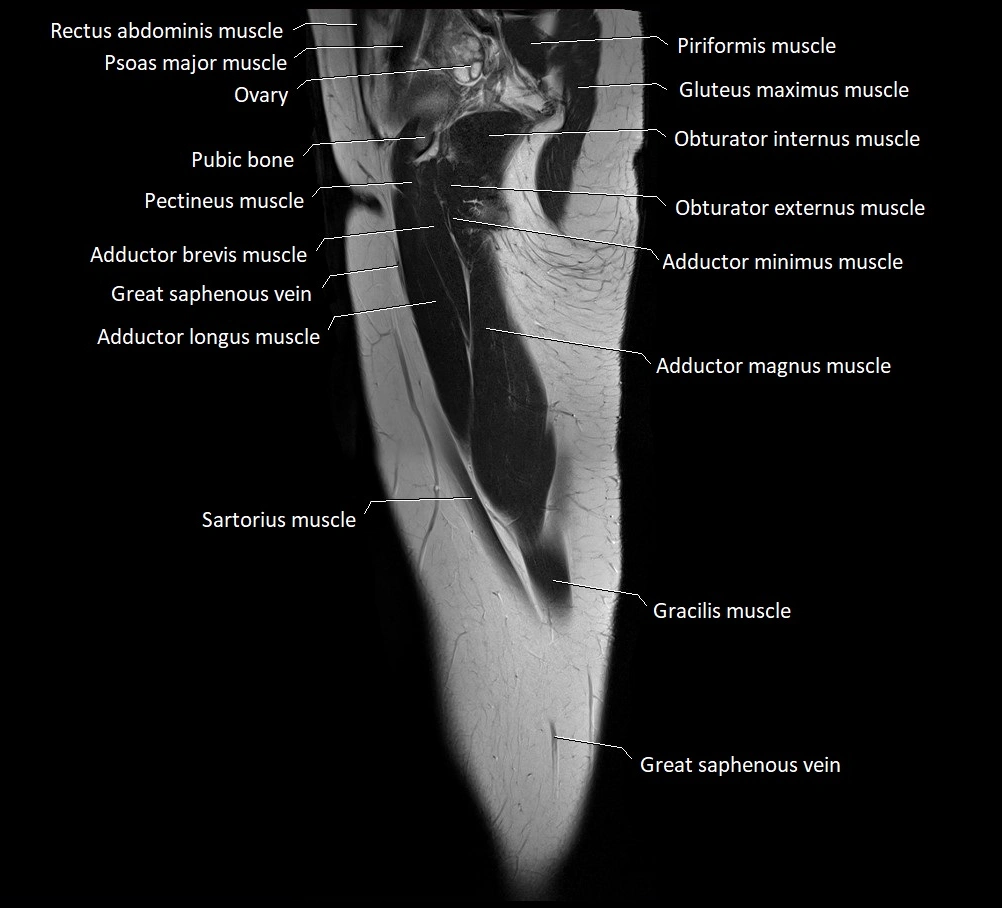

- Adductor brevis muscle

- Adductor longus muscle

- Adductor magnus muscle

- Adductor minimus muscle

- Gracilis muscle

- Obturator externus muscle

- Obturator internus muscle

- Pectineus muscle

- Sartorius muscle